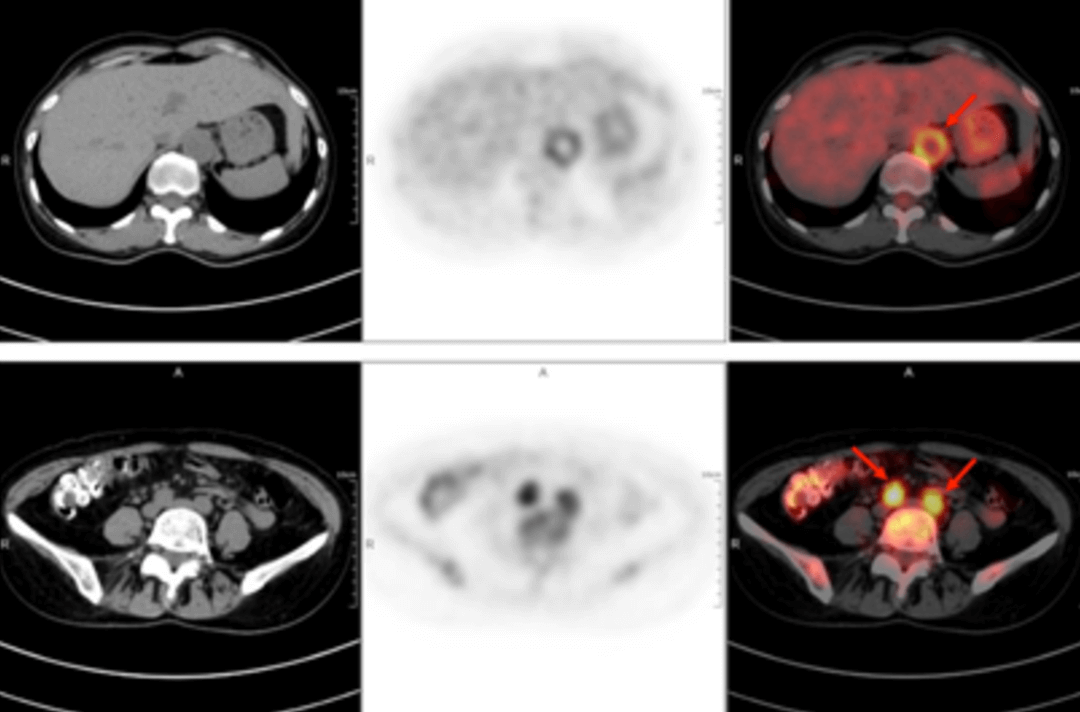

A 58-year-old women went to the hospital for intermittent fever for more than 40 days. Her highest body temperature was 38.9℃. Other symptoms included fatigue and shoulder joint pain which were especially acute in the afternoon and at night without cold, chills, sputum, hemoptysis, chest pain, chest tightness and shortness of breath. After two weeks of intravenous administration of "cephalosporin antibiotics" there was no improvement, and intermittent fever continued. The outpatient clinics noted the patient had "fever of unknown origin." There were no obvious diagnostic features upon physical examination. The results of a routine blood test were as follows: erythrocyte sedimentation rate in the first hour: 72mm; high-sensitivity C-reactive protein: 204. 20mg/l. Then, the patient had a whole-body F-FDG PET-CT examination to find the cause of the fever of unknown origin.

In the PET/CT images, wall thickening with increased glucose metabolism occurred in several parts of the body (bilateral internal carotid artery, common carotid artery, brachiocephalic trunk, bilateral subclavian and axillary arteries, thoracic aorta, abdominal aorta, bilateral common iliac artery, internal iliac artery, external iliac artery and femoral artery), which was considered to be caused by inflammatory changes. Combined with the patient’s medical history, clinical symptoms, examination and imaging findings, she was diagnosed with T.A. After standardized anti-inflammation treatment, her body temperature dropped and her condition improved.